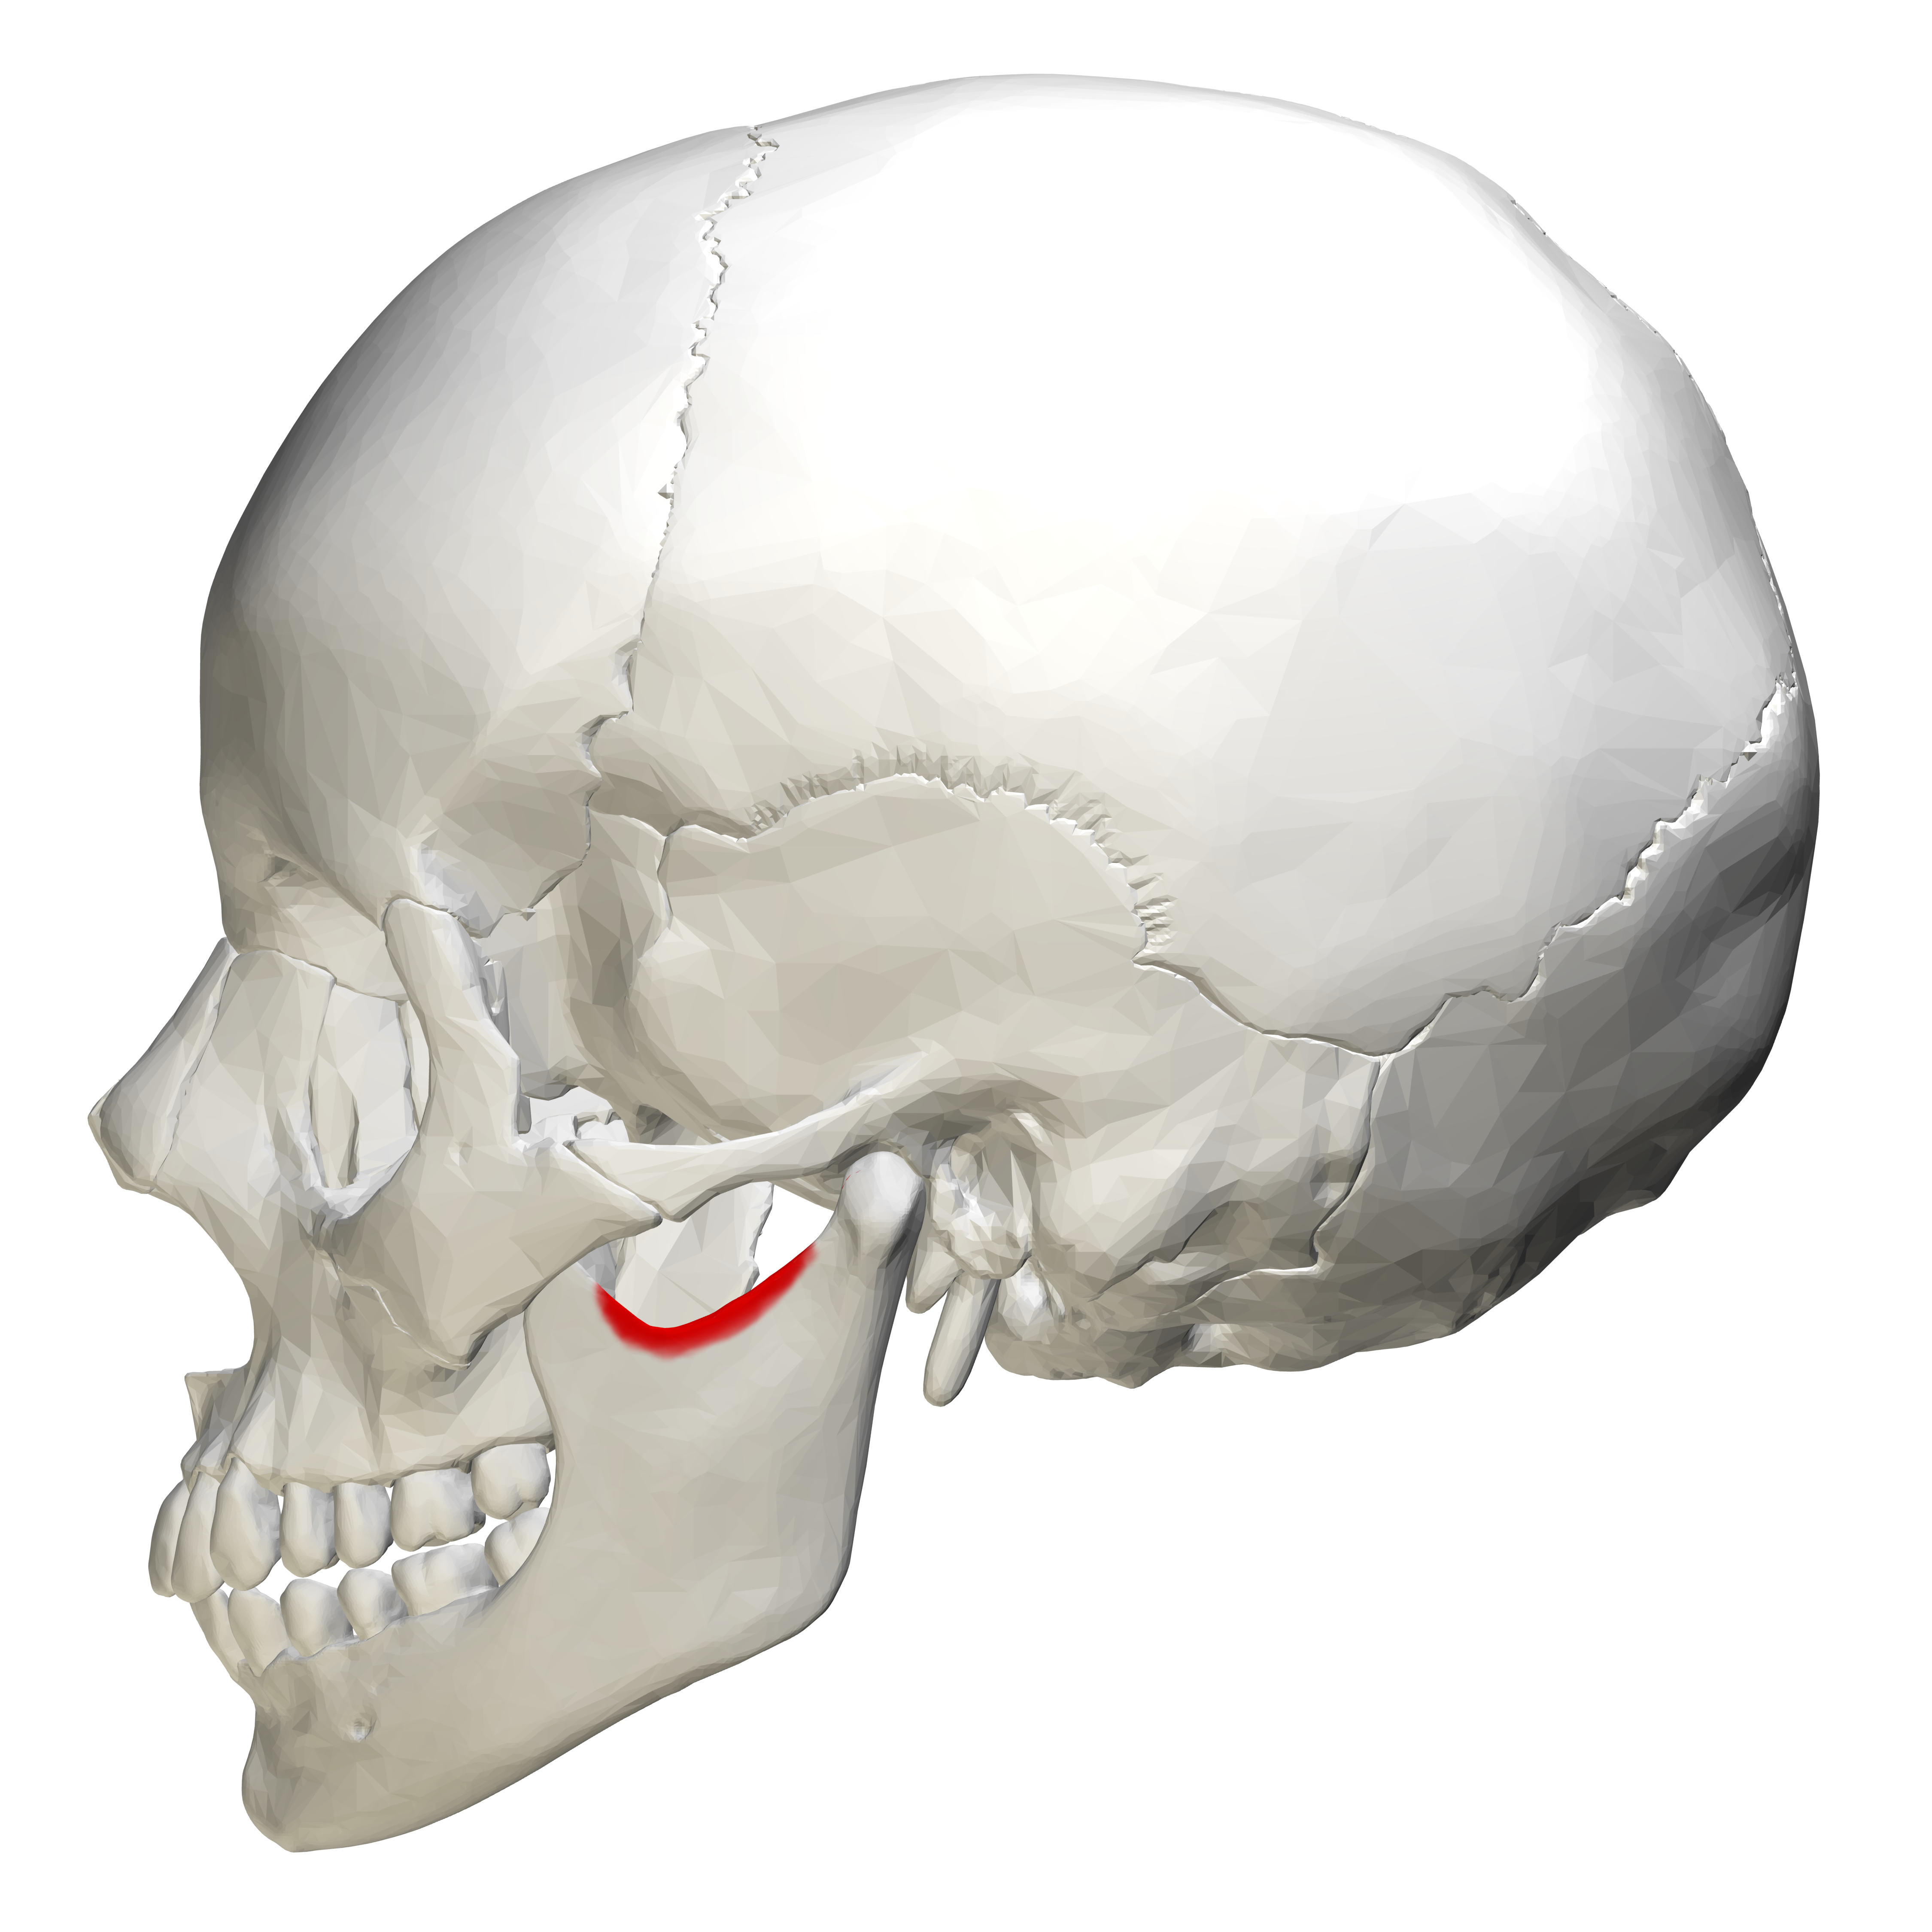

sigmoid notch

curved depression between mandibular condyle and coronoid process of mandible

radiopaque, not seen